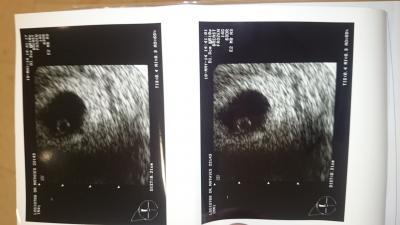

Ich bin soooo Happy, erst der nette neue FA, er war gar kein Vergleich zu der Ärztin auf die ich am Freitag gestoßen bin! So ein lieber und netter Arzt. Sogar seine Handynummer hat er aufgeschrieben falls am Wochenende mal was ist. Dann hat er uns den Zwerg gezeigt. Ganze 2 mm misst er schon und das Herzchen pochert vor sich hin. Die Schwangerschaft ist bestätigt und meinen Mutterpass habe ich auch mit bekommen

Die ersten Babyfotos habe ich im Anhang

Tolles Bildchen sieht aus wie meins